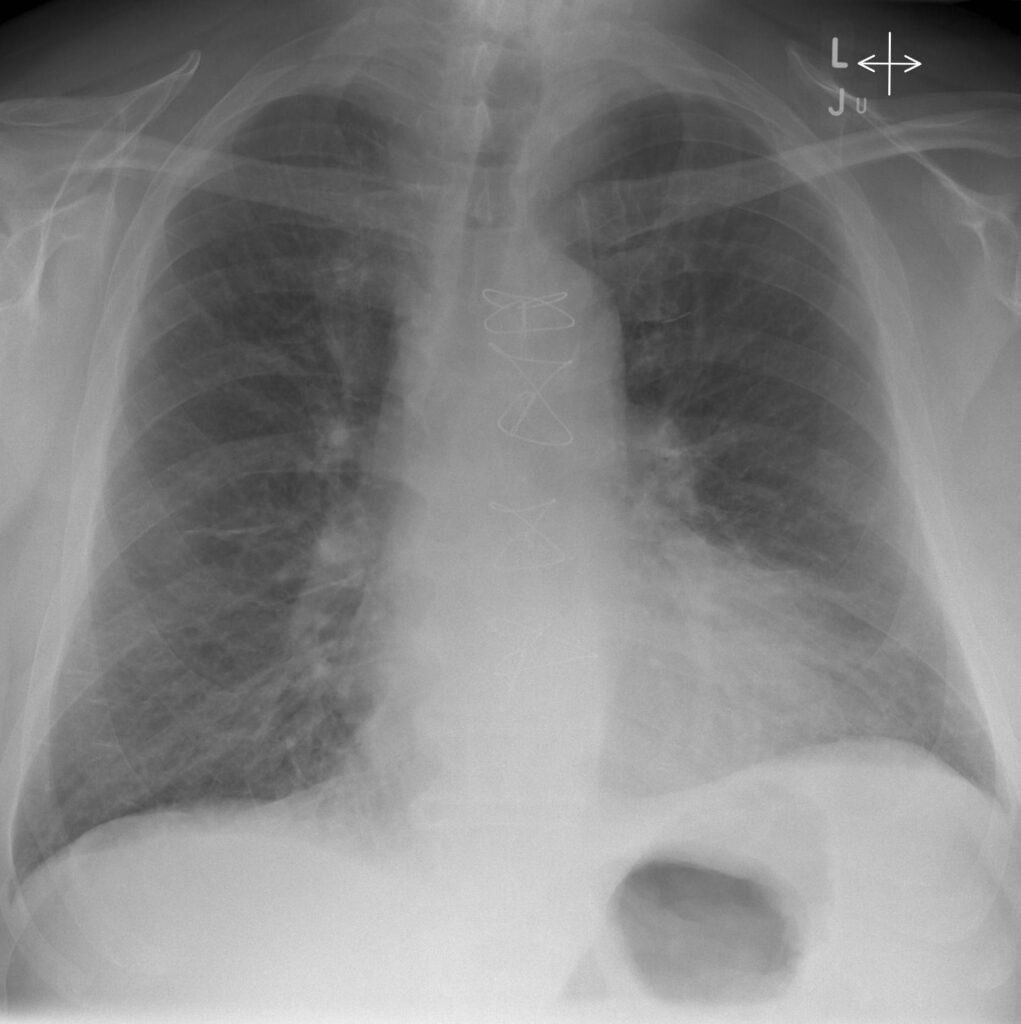

Si notino i segni di ridistribuzione vascolare verso i campi superiori e l’ingrandimento secondario alla congestione di entrambi gli ili polmonari definito “ad ali di farfalla”.

La radiografia del torace può mostrare segni di congestione interstiziale (linee di Kerley B), l’edema alveolare ad “ali di farfalla” e quote di versamento pleurico bilaterale.